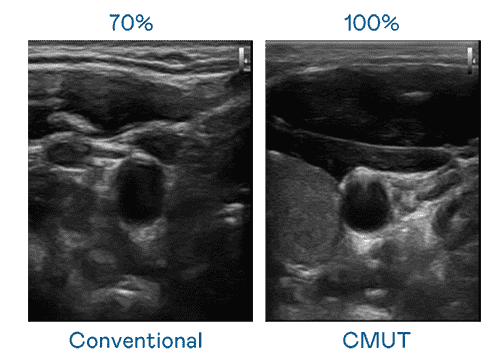

CMUT 技术是一种用电容式微机电元件来产生超音波讯号的技术。。。。与传统 PZT 压电式技术相比,,,,CMUT 频宽增加 30%,,,更宽频的超音波讯号让影像解析度大幅提升,,,,是实现高影像品质医疗超音波扫描、、、、促进精准医疗发展的关键技术。。。

大频宽带来超清晰影像

超音波影像的解析度高低,,首先取决于探头能发出的讯号频宽。。人生就是博 CMUT 可提供高清晰的超音波讯号,,,,提供高频宽、、、、高灵敏度、、影像纹理细节更高的超音波影像,,,协助医护人员缩短影像判读时间及利用精准的医疗影像进行诊断。。。